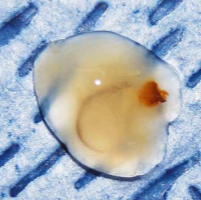

otoscopic examination and performed a myringotomy. (See specimen of

mucus at right.) He found no evidence

of inflammation or infection. He diagnosed: (a) primary secretory otitis

media (PSOM), causing the peripheral vestibular signs; (b)